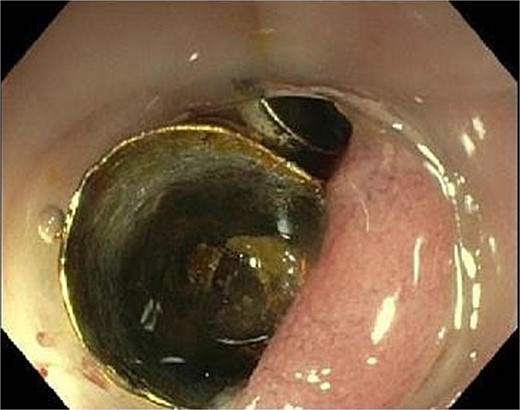

Computed tomography (CT) showed a foreign body in the sigmoid colon with adjacent fluid collection (Fig. 1). Due to vesical air inclusions, a sigmoido-vesical fistula was suspected. When further asked, the patient recalled that she had lost her denture 3 months ago at the Christmas market in December 2022. Colonoscopy revealed the impacted foreign body at 35 cm from anal verge with swollen and scarred stenosis of the sigmoid colon (Fig. 2). Endoscopic retrieval of the metal denture was not possible.

Endoscopic view showing the metal denture at 35 cm from anal verge with swollen and scarred stenosis of the sigmoid colon.